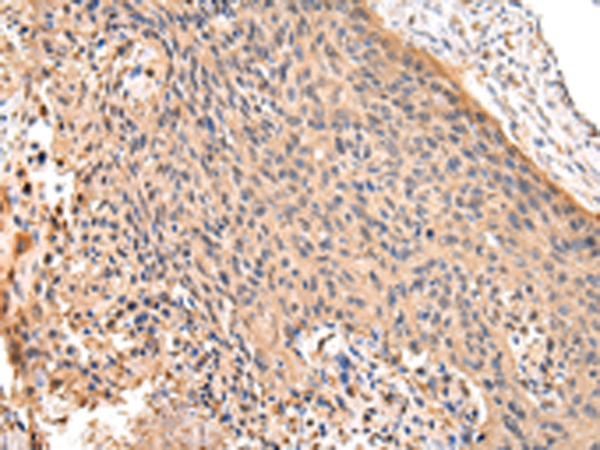

分类: 科研抗体货号: P11283别名:应用: WB,IHC反应种属: Human, Mouse